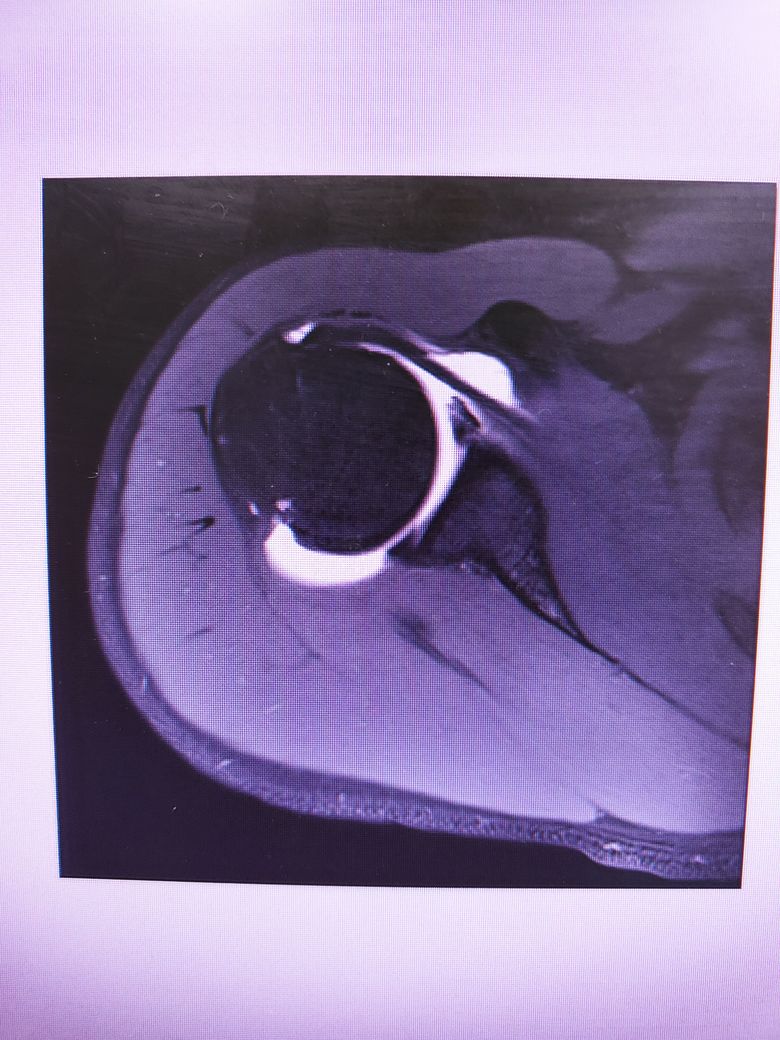

방카르트인지 한번 봐주시겠어요?

어깨를 움직일때 뒤쪽에 깊숙한 통증이있습니다.

염증인거 같긴한데 와순파열은 아닐지 걱정됩니다.

다음 사진에서 방카르트 소견이 있는 건지 봐주실 수 있을까요

• 4번 째 사진

MRI 4컷만 가지고는 방카트 병변을 명확하게 진단하기 어렵습니다.

현재 사진만으로는 방카트로 보이지는 않습니다.

사진 몇 장으로는 판단하기 어렵습니다.

해당 병원에 내원하셔서 MRI 영상에 대한 판독을 받으시기를 바랍니다.